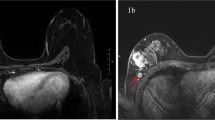

Clinical trials need to recruit large numbers of patients to achieve sufficient statistical power to detect a treatment effect. The most efficient way to do this is via multicentre studies, allowing suitable subjects to be drawn from a much larger patient population. One major disadvantage of multicentre trials in the neoadjuvant setting is that the post-treatment excisions are reported by a variety of pathology departments, with large variation in specimen handling protocols and reporting styles. At present, there are no established national guidelines in the United Kingdom for the histopathological handling of surgical tissue from neoadjuvant cases, and the reporting of neoadjuvant chemotherapy breast specimens. In the literature, there are several different systems for the histological grading of chemotherapy response (Marchio and Sapino, 2011). Many of the suggested systems in common use, rely on a comparison between tumour cellularity of the pre-treatment core biopsy and the post-treatment resection specimen (Figure 1), with the grade of response determined by the reduction in overall cellularity (Chevallier et al, 1993; Sataloff et al, 1995; Smith et al, 2002; Ogston et al, 2003; Pinder et al, 2007). The MD Anderson group have proposed an alternative system, the Residual Cancer Burden (RCB), that derives a score based on tumour bed volume, average tumour cellularity, number of involved lymph nodes and the size of the largest metastasis (Symmans et al, 2007). They have shown a relationship between RCB and survival outcome. The score relies on absolute cellularity post-treatment, without considering the change from pre-treatment cellularity. Traditional tumour grading systems used in the adjuvant setting, including the Nottingham Prognostic Index (NPI) and the TNM system using the prefix ‘y’ to indicate neoadjuvant treatment, have also been shown to retain their prognostic value post-chemotherapy (Chollet et al, 2003; Carey et al, 2005).

Histopathology reports were requested for all trial patients from 92 centres as per the trial protocol. The reports were received by the trial co-ordinating centre and were anonymised with respect to all patient details, with only the neo-tAnGo trial number available to reviewers. The reports were then independently reviewed by two study investigators, the study histopathologist (EP) and the chief investigator of the study, a medical oncologist (HME). A central pathology review form was completed by each reviewer, collecting information on the laterality of the surgery; whether or not there had been a pCR in the breast (yes/no/unknown); the absence of metastatic disease in the axillary lymph nodes post-treatment (yes/no/unknown); the nature of axillary lymph node surgery (pre-treatment sentinel lymph node biopsy (SLN), post-treatment SLN and/or post-treatment axillary clearance (ALND)) and the number of lymph nodes sampled and the number of lymph nodes involved for each type of surgery. In cases where there had not been a pCR in the breast, the reports were further subcategorised as minimal residual disease (>90% response), chemotherapy response present, no chemotherapy response and no comment regarding chemotherapy response. A subset of cases was also independently reviewed by a third party (KW). Following collation of the review findings, cases in which there was disagreement between reviewers were discussed jointly and a consensus was reached. Further information was recorded by one of the reviewers (EP) regarding the number of histology blocks taken in cases with a pCR, whether there was formal grading of chemotherapy response and what system was used, and whether or not the reports commented on the presence or absence of changes suggesting response to chemotherapy in the axillary lymph nodes (Figure 2).